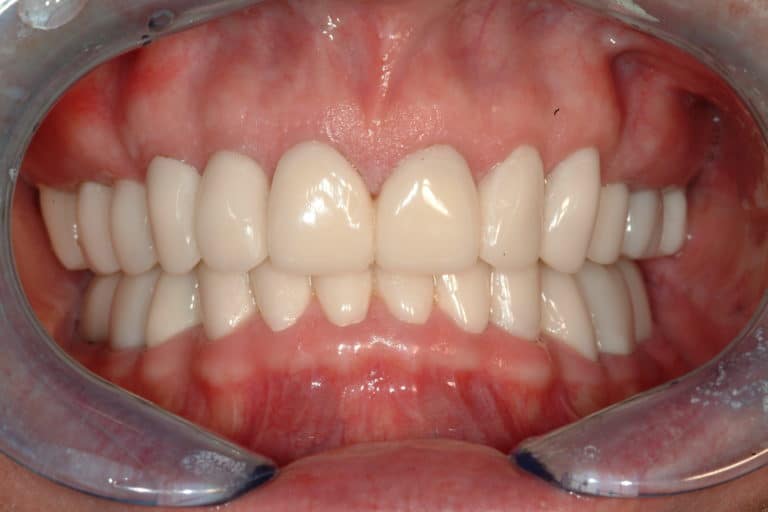

Before & After Gallery

Individual results may vary.